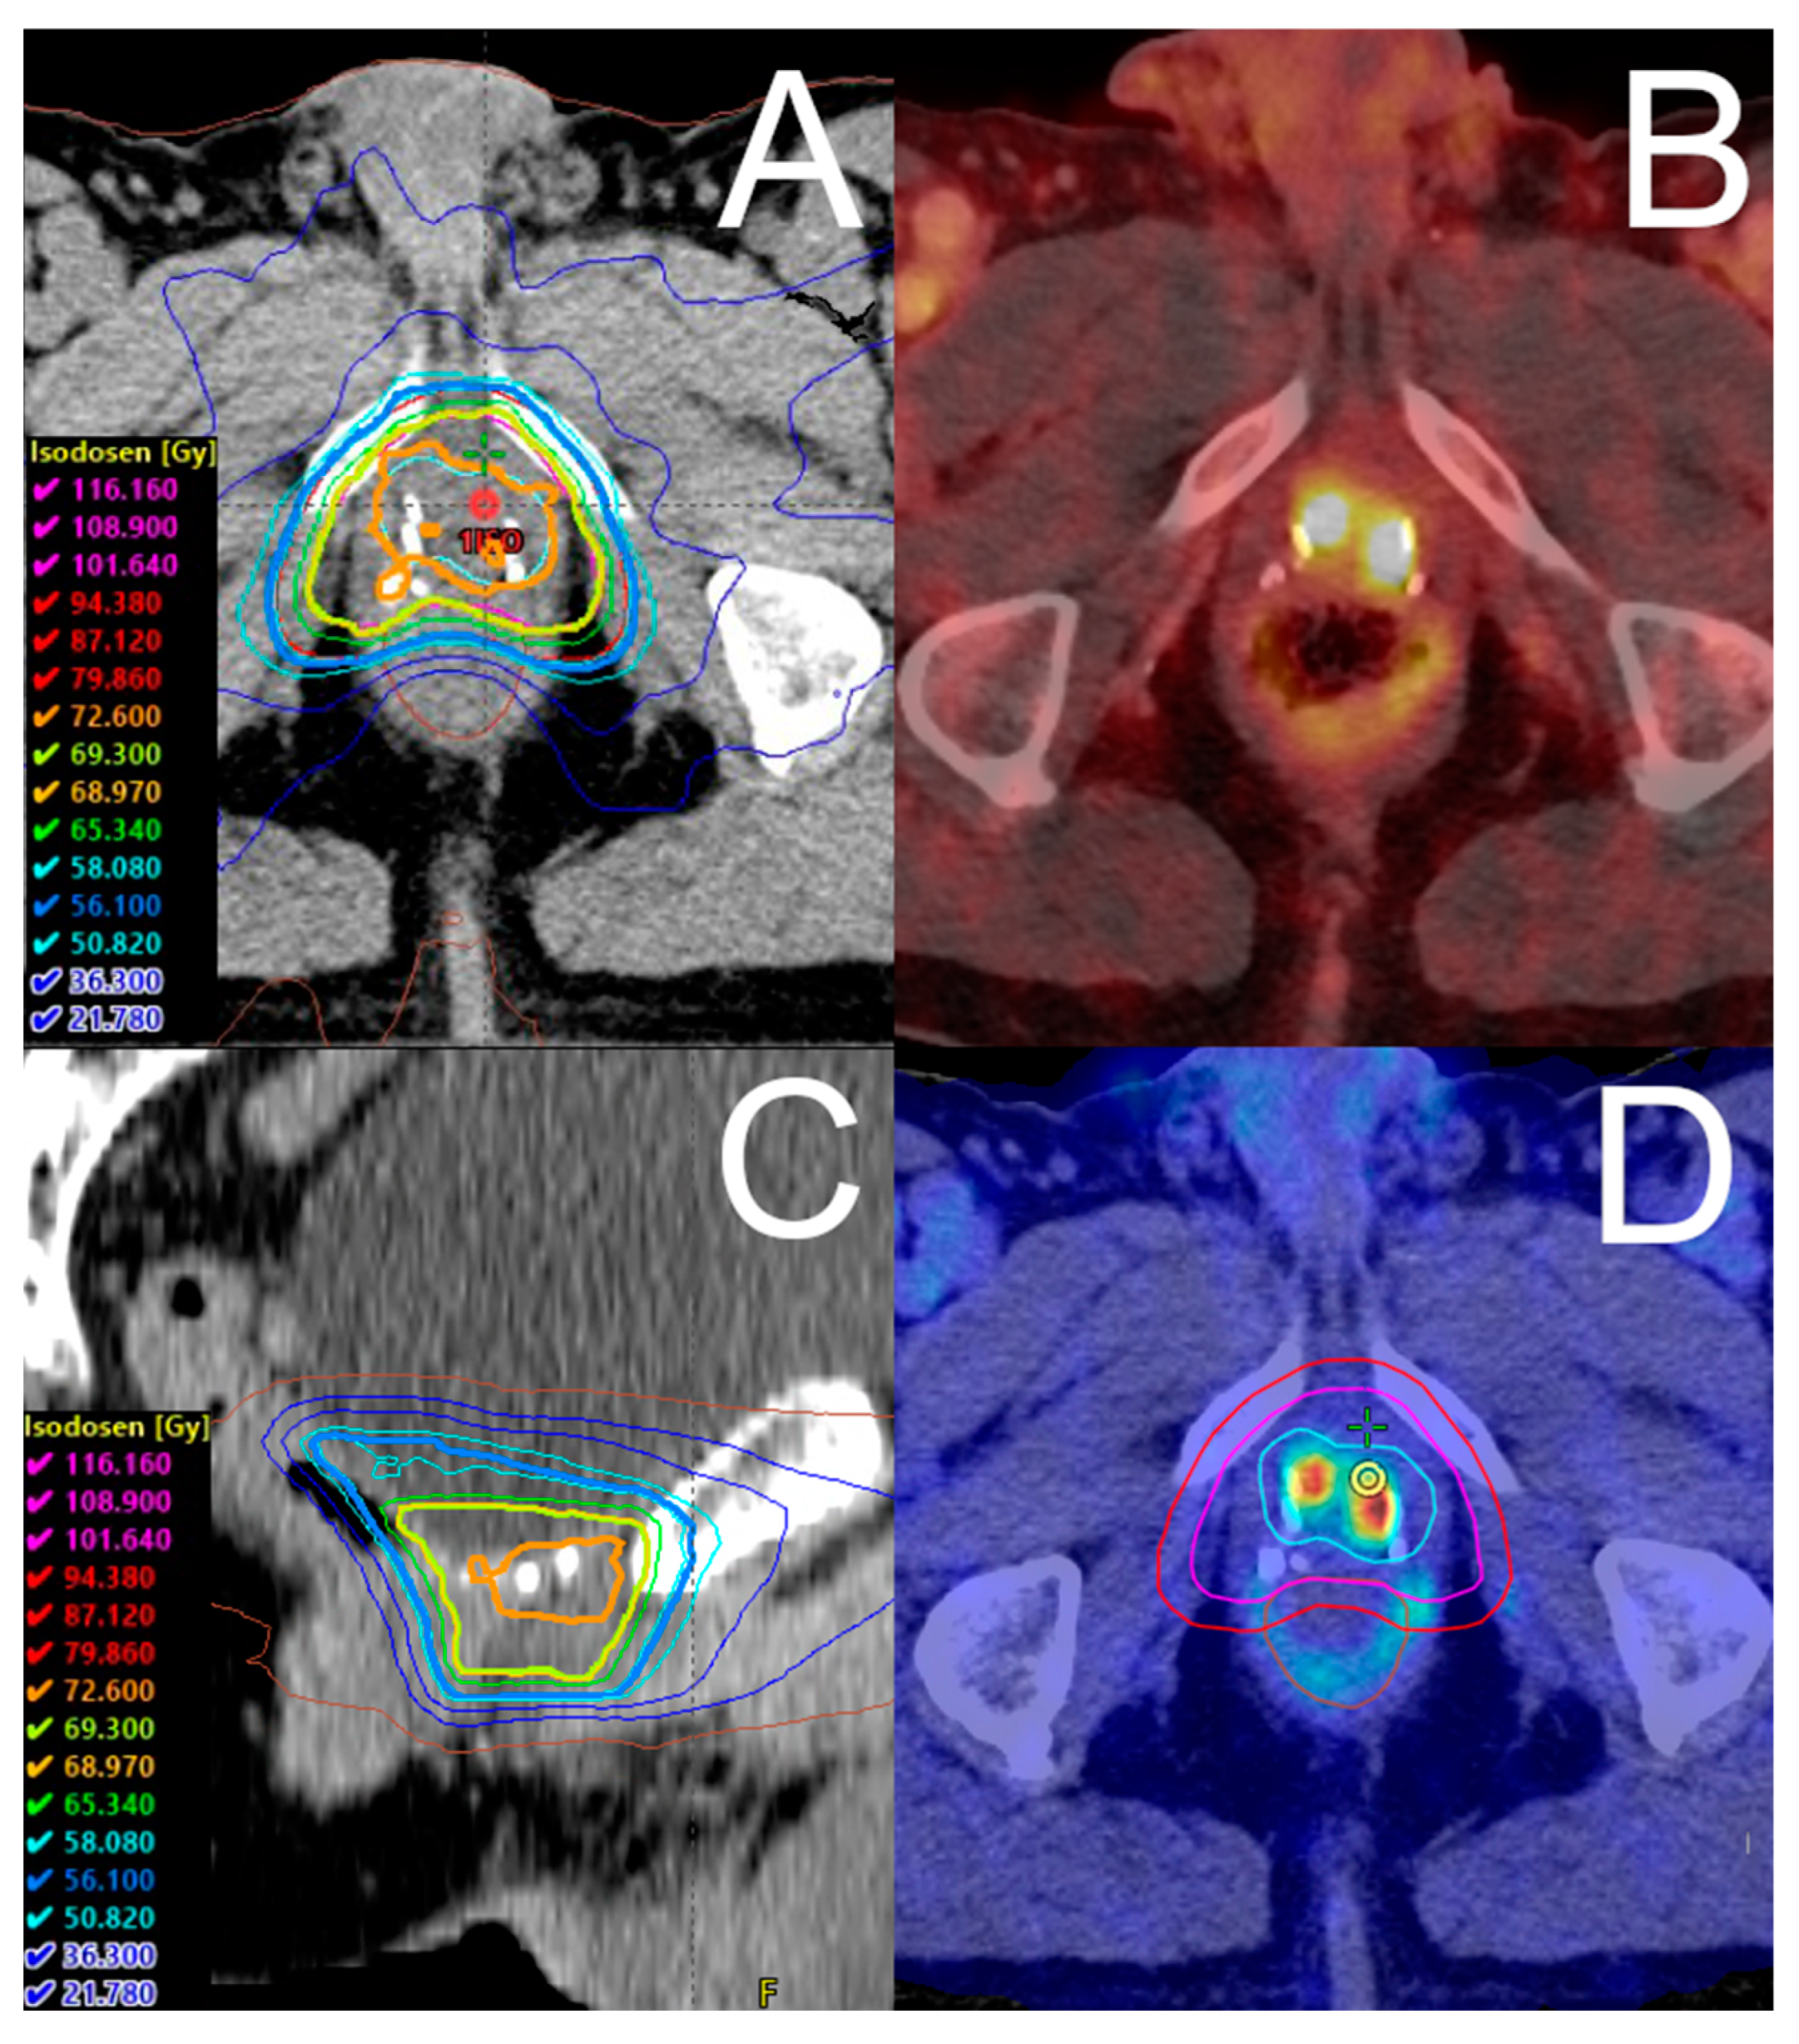

| SIB concept, n (%) | |

| Two dose levels | 31 (52.5) |

| Three dose levels | 28 (47.5) |

| Number of fractions | 33 (33, 33) |

| Prostate bed PTV dose (Gy) | 56.1 (56.1, 56.1) |

| Prostate bed PTVBoost1 dose (Gy) | 69.3 (69.3, 69.3) |

| Prostate bed PTVBoost2 dose (Gy) | 72.6 (72.6, 75.5) |

| Lymph node PTVBoostLN (Gy) | 66.9 (61.4, 69.3) |